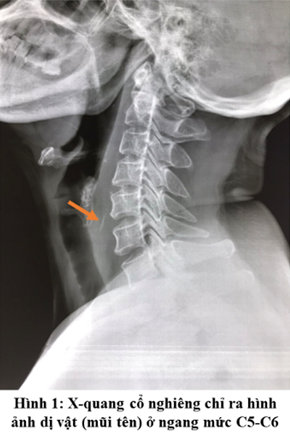

Bệnh nhân L.T.T.T, nữ, 49 tuổi, địa chỉ phường An Tây, Huế, vào viện với lý do nuốt đau, sưng nề vùng cổ trái. Bệnh nhân khai đã mắc xương cá đuối 3 ngày trước đó, không đi khám và xử trí gì và được chỉ định nội soi hạ họng - thanh quản không phát hiện dị vật, sau đó được chụp phim Xquang cổ nghiêng phát hiện dị vật ở ngang mức C5-C6.

Bệnh nhân được phẫu thuật nội soi thực quản ống cứng để lấy dị vật, tuy nhiên, không phát hiện dị vật trong lòng TQ. Bênh nhân được thực hiện xét nghiệm bổ sung bao gồm siêu âm, CT scan và đã phát hiện dị vật đã di chuyển ra tam giác cổ sau. Thêm vào đó, trên đường di chuyển của mình dị vật để lại hình ảnh dò các bóng khí từ TQ đến ổ thâm nhiễm có dị vật cản quang.